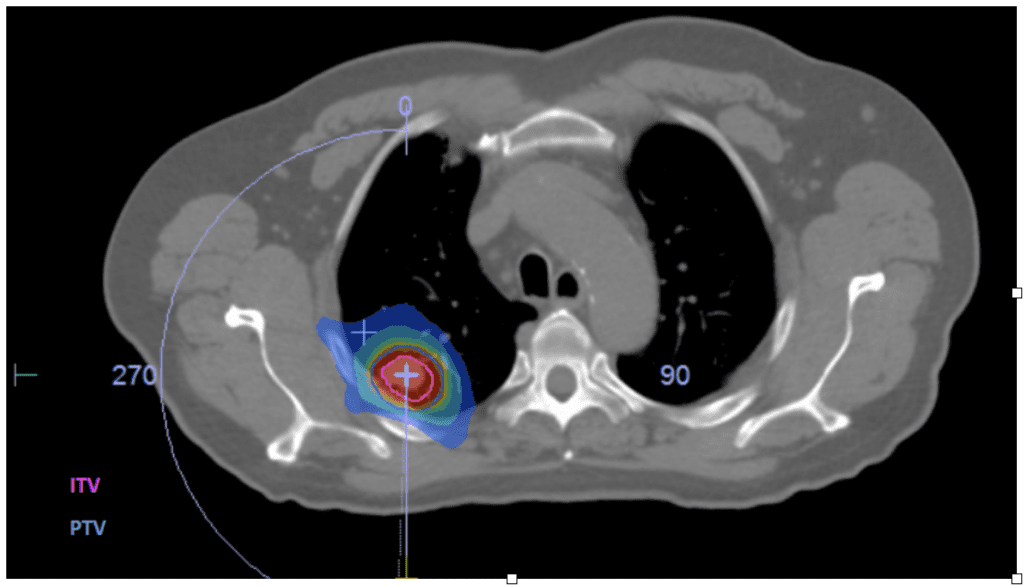

Exemple de dosimétrie d’une radiothérapie stéréotaxique d’une métastaste osseuse à Chénieux

La radiothérapie stéréotaxique sur tumeur pulmonaire a été débutée en avril 2019. Cette technique, plus compliquée du fait des mouvements respiratoires, est rendue possible par un plateau technique associant un scanner dosimétrique 4D (tenant compte des différentes positions de la tumeur en fonction du cycle respiratoire) associée à une imagerie de positionnement sur l’accélérateur également équipée une technologie 4D (XVI SymmetryTM de Elekta) mais également grâce au contrôle du positionnement surfacique AlignRT® qui permet un contrôle en direct, pendant toute la durée de la séance de traitement, du positionnement de la surface du patient (et donc son ampliation thoracique). Cette technique est devenue elle-aussi depuis une pratique courante pour les petites métastases pulmonaires et les petits cancers pulmonaires primitifs non opérables.